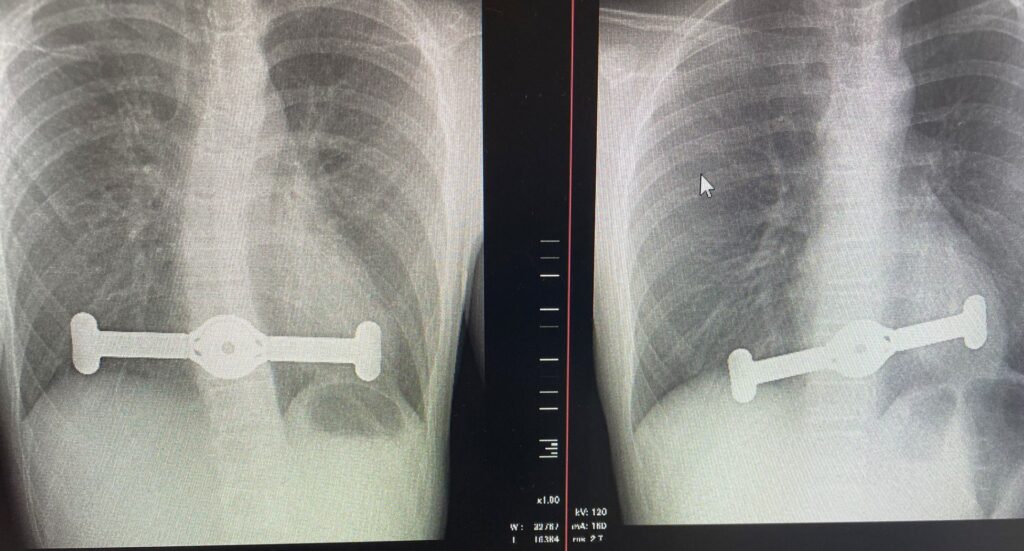

Rentgeno nuotr. Krūtinės ląstos įdubimo operacija